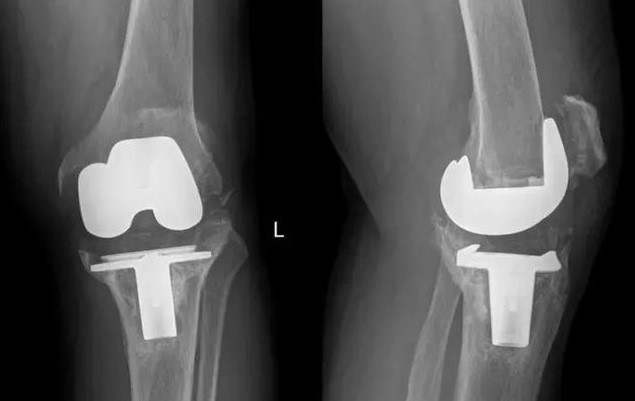

2017年11月,我國完成了全球首例個性化3D打印鉭金屬墊塊植入的全膝關節(jié)翻修手術;2018年,LPW科技公司與環(huán)球先進金屬集團有限公司(GAM)宣布達成合作協(xié)議,圍繞金屬鉭的增材制造技術可為醫(yī)療外科、牙科、軍事、航空航天以及其他市場領域提供服務。鉭金屬通過3D打印制成的多孔鉭植入體,相較常見的多孔鈦植入物,具有更好的生物力學適配性、并具有接近人骨的彈性模量。在植入穩(wěn)定性上,具有較大優(yōu)勢。